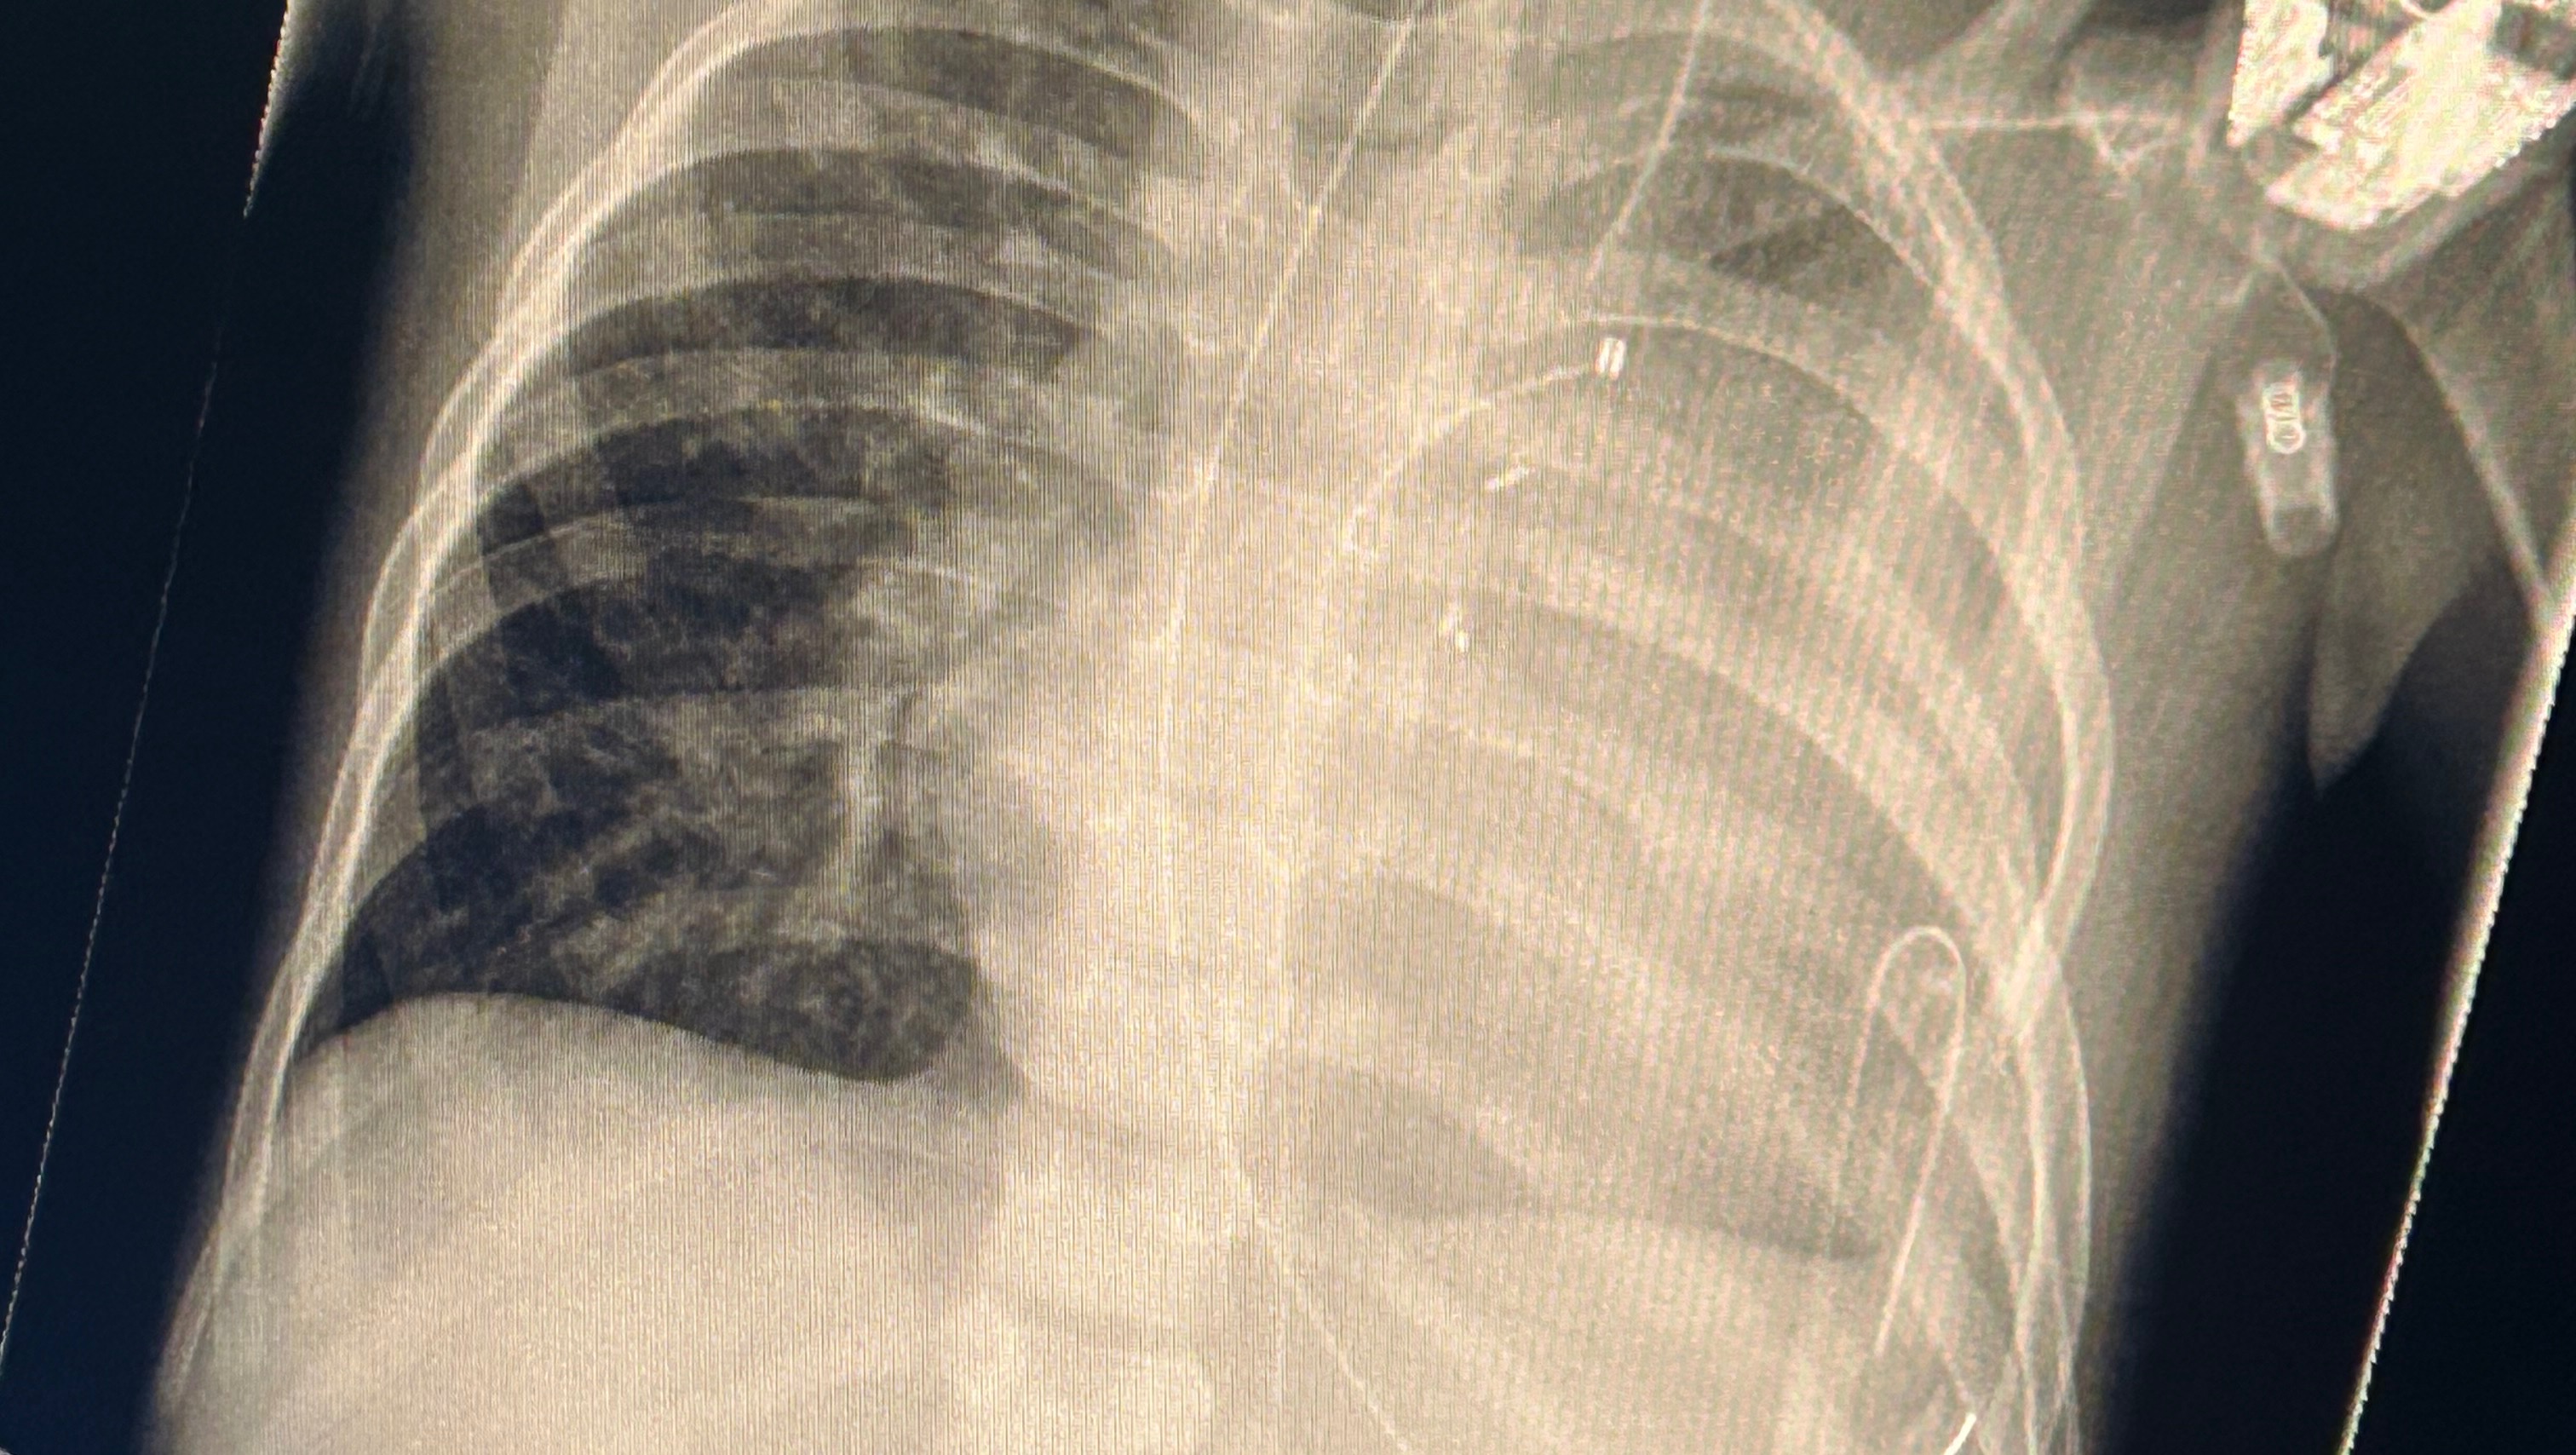

Scarlett developed an acute kidney injury, followed by a severe lung reperfusion injury — a condition where blood flow returning to the lung causes inflammation and damage. Her left lung collapsed, leaving only small pockets of open airways struggling to function. Breathing on her own became impossible. Machines had to step in, doing the work her tiny body could not.

Since that day, Scarlett has remained in the Paediatric Intensive Care Unit, reliant on a ventilator to breathe. Each day blends into the next, measured not by hours but by oxygen levels, chest scans, and whispered conversations between doctors. More than a week has passed, and her lung is still fighting to recover.